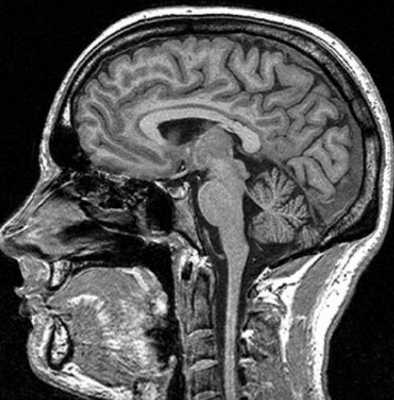

МРТ костей черепа что показывает

Магнитно-резонансная томография базируется на способности магнитного поля изменять состояние атомов водорода в молекулах воды. Процедура информативна относительно мягких тканей, насыщенных жидкостью. Структуры организма с низким содержанием воды на снимках отражаются плохо. МР-томограф фактически «не видит» костную ткань. По этой причине рутинная диагностика переломов включает рентгенографию и КТ (в экстренных, спорных либо сложных ситуациях). При травмах головы стандартное обследование с помощью Х-лучей нередко сочетают с магнитно-резонансной томографией. В зависимости от того, что показывает МРТ костей черепа, дополняют тактику лечения, основанную на результатах КТ. Процедура дает информацию о состоянии мягких структур и влиянии на последние травм.